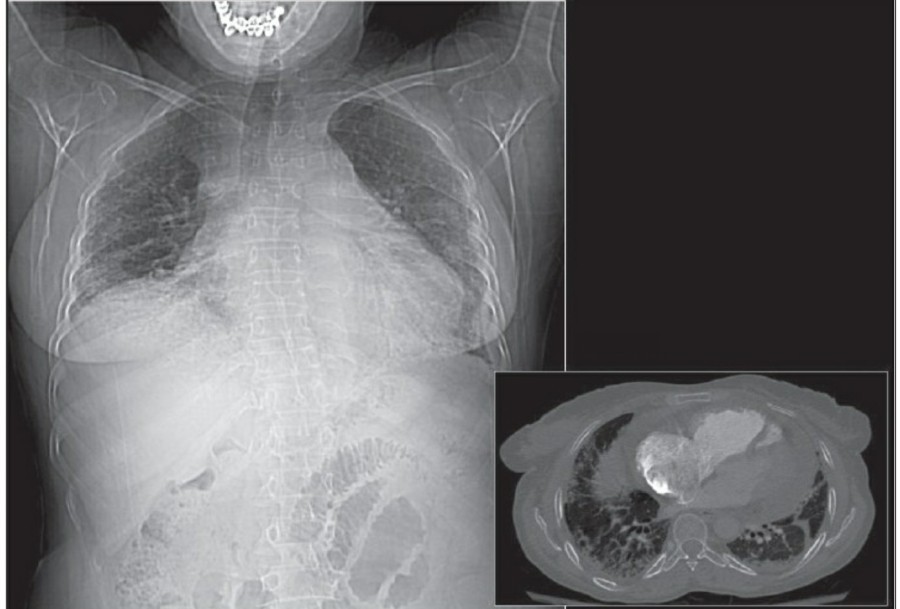

Pneumomediastinum은 mediastinum 안에 공기가 있는 경우를 일컬으며, intubation된 환자에서 구심적으로(centripetally) pulmonary interstitial dissection이 일어나는 경우와 관련이 있다.

또한 Mediastitnal air는 major airway 손상으로 인한 leakage나 retroperitoneum으로부터 fascial plane을 따른 air dissection에 의해 발생하기도 한다. Pneumomediastinum은 목까지 공기가 진행이 가능하고, pneumopericardium은 이와는 다르게 심장의 밑 부분으로 진행한다. Pneumomediastium은 일반적으로 무증상이지만, 간혹 청진 시 restrosternal crunch가 들릴 수 있다. Chest X ray상에서 공기가 major vessel 주변이나 SVC의 medial border, azygos vein에서 surrounding lucency로 보일 수 있다. 또한 aortic knuckle, descending aorta, pulmonary artery의 윤곽으로 나타날 수도 있다. Posteromedial pneumomediastinum은 주로 esophageal rupture의 결과로 나타날 수 있는데, praspinal costophrenic angle과 left diaphragm의 praietal pleural로 air dissection이 가능하다. 이 결과 V-sign of Naclerio라고 불리는 V-shaped lucency가 발생한다.